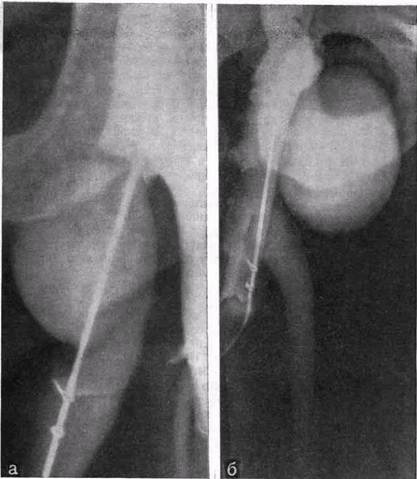

Рис. 25. Неравномерные подклапанные расширения большой подкожной вены (ретроградное контрастирование).

очевидно, поэтому в глубоких венах наблюдается равномерная дилатация. В поверхностных венах, напротив, подкожная жировая клетчатка не ограничивает возможность неравномерных, иногда весьма крупных.патологических расширений. Неравномерные расширения вен—вариксы—как характерный признак заболевания нашли отражение в его названии. В магистральных подкожных венах такие расширения образуются вблизи ве- __ нозных клапанов (рис. 25, а, б).

Механизм возникновения таких расширений мы объясняем следующим образом: при функциональной и особенно анатомической неполноценности венозного клапана ретроградный поток крови, проходя через щель между створками, отклоняется преимущественно в какую-либо одну сторону. Таким образом, струя крови направлена на один из участков венозной стенки, что и приводит к ее перерастяжению, выпячиванию, иногда весьма значительному.

Одностороннее выпячивание возникает, когда щель между клапанными створками расположена эксцентрично или когда имеются анатомические изменения одной створки, или анатомически изменены обе створки, но одна из них поражена больше, а другая меньше. В таких обстоятельствах щель в анатомически неполноценном клапане расположена эксцентрично, что и обусловливает направленность струи крови преимущественно на одну из стенок вены. Венозная стенка наиболее тонка в области синусов венозных клапанов, однако при варикозной болезни патологически расширяются не эти отделы венозной стенки, а участки ее, расположенные дистальнее клапана, что лишний раз свидетельствует о повреждающей роли ретроградного турбулентного кровотока.

Помимо локального давления струи крови на стенку вены, под воздействием турбулентного кровотока оказывается весь сегмент вены дистальнее клапана. Когда имеет место ретроградный кровоток, можно говорить об эффекте форсунки, так как струя крови проходит через неполностью сомкнувшиеся створки клапана. Патологическое расширение сосудов возникает поэтому не перед участком сужения, а после него.